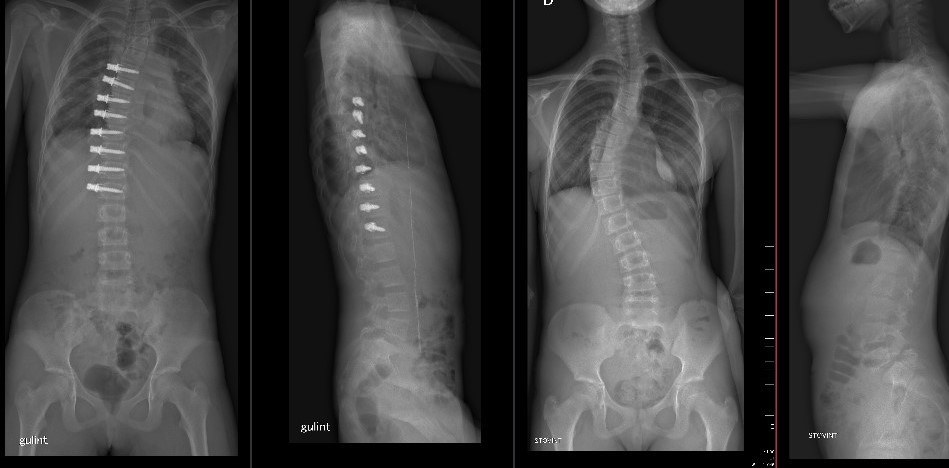

Stuburo operacijos rentgeno nuotrauka